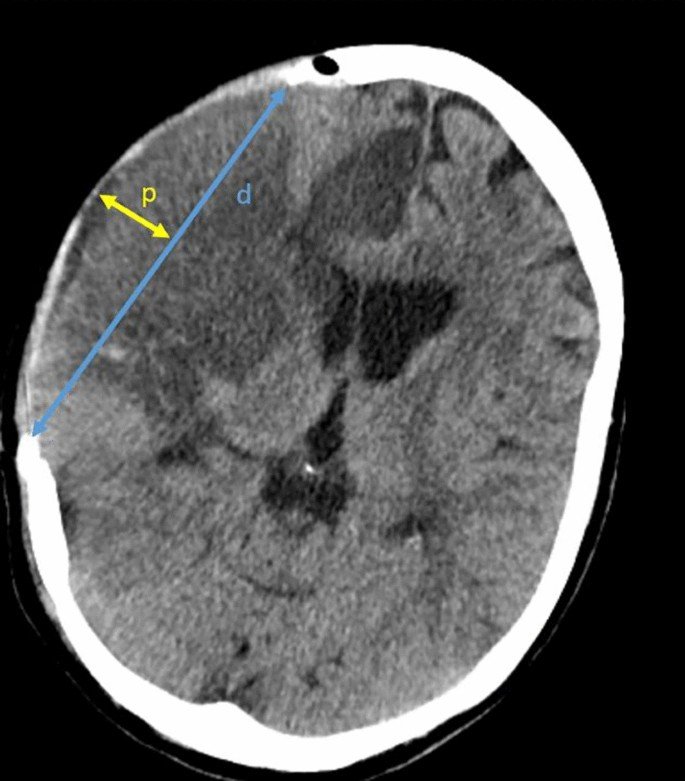

Spontano netraumatsko intracerebralno krvarenje (ICH) je drugi najčešći uzrok moždanog udara, odmah iza ishemijskog, i čini oko 10–20% svih slučajeva. Ova retrospektivna, multicentrična, deskriptivna opservaciona studija analizira ishode nakon ICH i dekompresivne kranijektomije (DC) kod starijih odraslih osoba (>65 godina), koji su lečeni u četiri nemačke zdravstvene ustanove koje su izvele ovo istraživanje.

Klinički ishodi su prvi put evaluirani pri otpustu iz bolnice, a zatim i 12 meseci nakon operacije, pomoću Glazgovske skale ishoda (Glasgow outcome scale-GOS). Pacijenti su podeljeni u starosne grupe od ≤65 i >65 godina, te u kohorte sa povoljnim ishodom (GOS IV–V) i nepovoljnim ishodom (GOS I–III). 73,2% pacijenata je bilo starosti ≤65 godina, a 26,8% starijih od 65 godina. Prosečna starost je bila 53,3 godina. Tokom bolničkog lečenja, 24,4% pacijenata u grupi mlađih (≤65 godina) i 33,3% u grupi starijih pacijenata (>65 godina) je umrlo. Prosečno vreme između javljanja moždanog udara i hirurške intervencije je bilo 44,4 sata za grupu mlađih, i 27,9 sati u grupi starijih pacijenata.

Dvanaest meseci nakon intracerebralnog krvarenja i dekompresivne kranijektomije, približno 31% pacijenata je umrlo, a približno polovina pacijenata (46%) je zavisila od tuđe pomoći u obavljanju svakodnevnih aktivnosti. Ustanovljen je veoma visok rizik od nepovoljnog ishoda nakon intracerebralnog krvarenja i dekompresivne kranijektomije kod pacijenata starijih od 65 godina (73%), što znači da će na duži rok samo manji deo pogođenih starijih odraslih osoba imati zadovoljavajući ishod, koji pored preživljavanja podrazumeva i zadržavanje sposobnosti samostalnog obavljanja svakodnevnih aktivnosti.